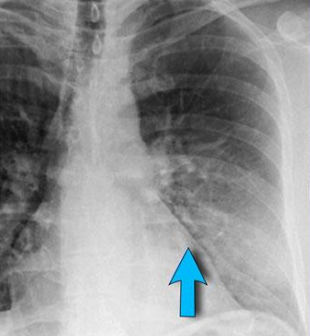

Esta es una radiografía de:

A

Mediastino